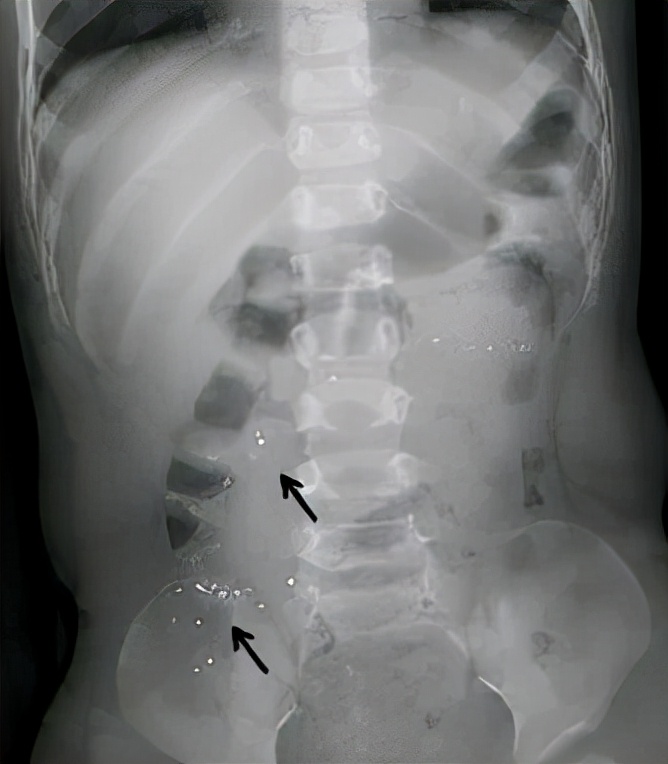

这不,西北妇女儿童医院近期就接诊了一位23个月大的小淘气,在父母给量体温时把体温计给咬破了!急忙之下,来影像科拍片检查,可以清楚看到肚子里的水银颗粒!

6、及时就医,必要时可以拍X线片观察下汞在胃肠道内的部位。